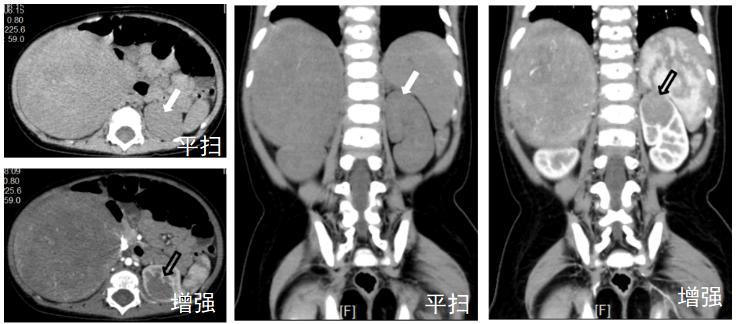

CT增强扫描应用于病变检出

上图,CT平扫左肾占位未见显示(白箭头),CT增强扫描提示左肾占位(黑色空心箭头),增强扫描如同“显影灯”,让平扫中隐匿的左肾占位(白箭)在增强后(黑色空心箭头)清晰显现。